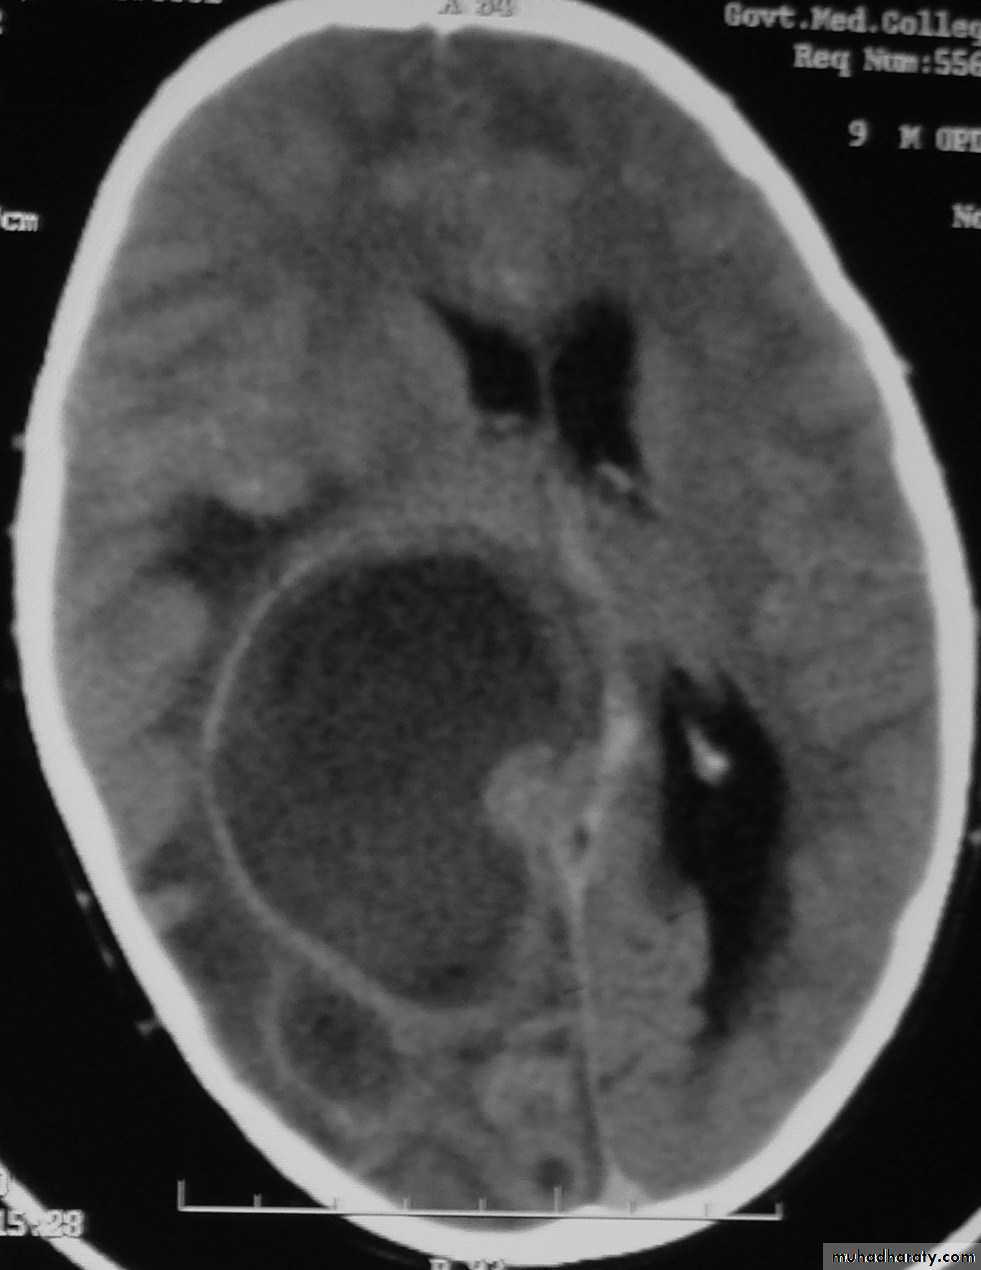

Bacterial Meningitis with cerebral oedema